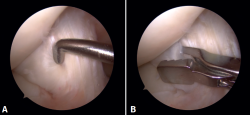

Figura 3. Visión artroscópica desde el portal anterolateral de la rodilla derecha. Se observa el quiste sinovial del ligamento cruzado anterior (LCA) en el fascículo posterolateral. A: visión con palpador diferenciando fibras del LCA sano del quiste; B: visión con la rodilla en posición “de cuatro” en la que se observa el pinzamiento del quiste en el espacio tibiofemoral lateral.

En ambos pacientes se realizó anestesia raquídea para realizar la cirugía y se utilizó manguito de isquemia a nivel del muslo. Se colocó al paciente en decúbito supino, utilizando un soporte en U en el tercio distal del muslo para la fijación de la extremidad. Se realizaron los portales artroscópicos habituales anterolateral y anteromedial, objetivando en la exploración diagnóstica de la rodilla la presencia de un ganglión localizado en el fascículo posterolateral del LCA (Figura 3) que, cuando se realizaban los movimientos de flexión y en posición de cuatro, se pinzaba en el espacio articular tibiofemoral externo. Para realizar la resección artroscópica del quiste se colocó al paciente en la posición “de cuatro”, facilitando la diferenciación anatómica de los fascículos anteromedial y posterolateral del LCA, tal y como proponen Hopper G et al.(4). Se realizó la disección y exéresis cuidadosa del quiste con una pinza basket, un terminal shaver de 4 mm y un terminal de ablación por radiofrecuencia (Figura 4). Al finalizar la resección del quiste, se realizó una nueva exploración dinámica de la rodilla, donde se evidenció la ausencia de pinzamiento entre el LCA, el cóndilo femoral y el platillo tibial lateral, a la vez que se comprobó la estabilidad del remanente del LCA (Figura 5).